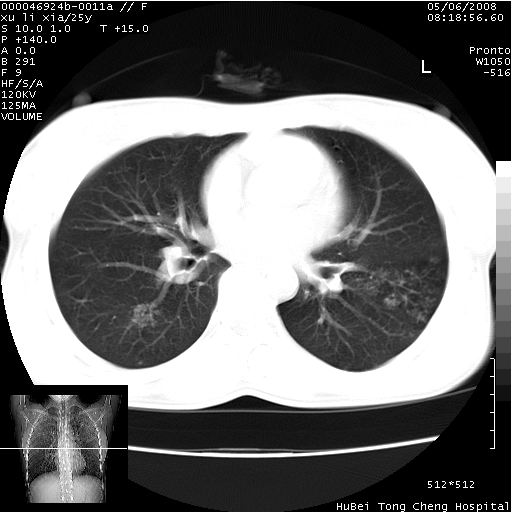

患者 女,25岁。因“左侧卵巢肿瘤”术前胸片偶然发现两肺病变。平素无明显不适,无呼吸系统症状及体征,无传染病史。

cr x线胸片提示:两肺感染性病变(结核可能性大)。

胸部ct轴位平扫(层厚10mm,螺距1.5,重建间隔10mm),图像如下:

(注:上级医院会诊胸部ct片——考虑为肺部真菌感染。)

病灶呈地图样分布于肺外围,与正常组织分界清晰+弥漫性磨玻璃影中见小叶间隔增厚呈碎石路样表现+年轻女性,无明显临床症状=肺泡蛋白沉积症?